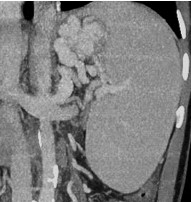

Hình 1: (A) Các vòng nối cửa chủ; (B) giãn TM phình vị trên nội soi và (C) trên MSCT